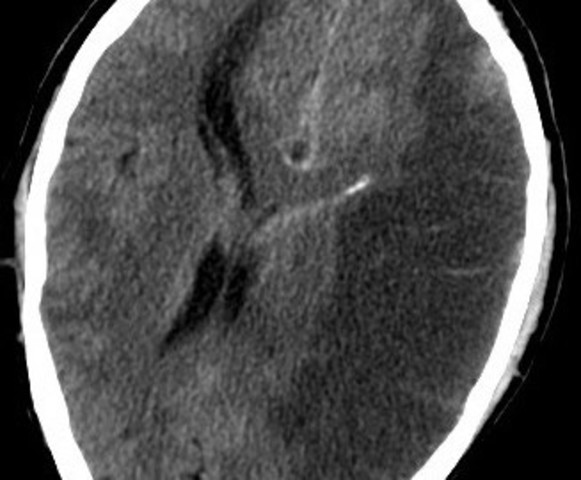

• Isquemia focal

Isquemia focal

La isquemia focal pasa cuando ocurre un accidente cerebrovascular. Esta isquemia tiene el beneficio de contar con vasos contralaterales. Esta circulación contralateral irriga las áreas indemnes durante un episodio de isquemia focal aportando suficiente sustrato a la región afectada, y así mantener la integridad de la membrana.